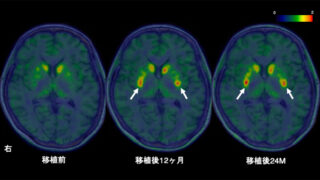

兵庫医科大学病院(兵庫県西宮市、病院長:難波光義)、および北海道大学病院(北海道札幌市、病院長:寳金清博)は、「羊膜間葉系幹細胞(以下、羊膜MSC)によるクローン病および急性移植片対宿主病(GVHD)に対する第I/II相医師主導治験」について、クローン病は2017年9月、急性GVHDは同年11月にそれぞれ厚生労働大臣へ治験届を提出しました。

クローン病(p.2)や急性GVHD(p.3)といった難治性疾患には、副腎皮質ステロイド剤や免疫抑制剤といった炎症・免疫を抑える薬が治療に用いられますが、すべての方に必ずしも有効ではありません。一方、MSCにも免疫を調整する作用があり、我が国では骨髄MSCが急性GVHDに対する再生医療等製品として既に実用化されています。兵庫医科大学病院および北海道大学病院の研究グループでは、骨髄MSCよりも、①幹細胞数が多く、②増殖能も高く、③採取に侵襲性のない「羊膜MSC」を用いた細胞治療研究を進めており、この度、世界で初めて「羊膜MSC」の治験薬製剤化に成功し、クローン病や急性GVHDに対する医師主導治験を開始するに至りました。